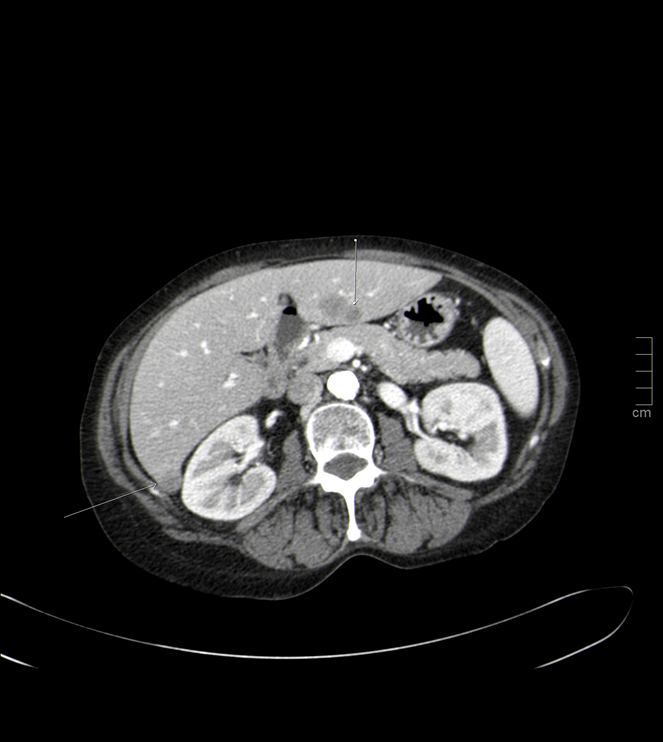

En el estudio de TC torácico se aprecia una masa hiliar superior derecha, de unos 4 x 5 cm, que se extiende hacia LSD, con zona de consolidación, necrosis y cavitación indicativa neoplasia de pulmón con neumonitis cavitada periférica en LSD, con bloques adenopáticos, de hasta 3 cm paratraqueales superiores pretraqueales con afectación también a nivel subcarinal.

En cortes inferiores, se encuentra otro hallazgo relevante y que corrobora el diagnóstico: